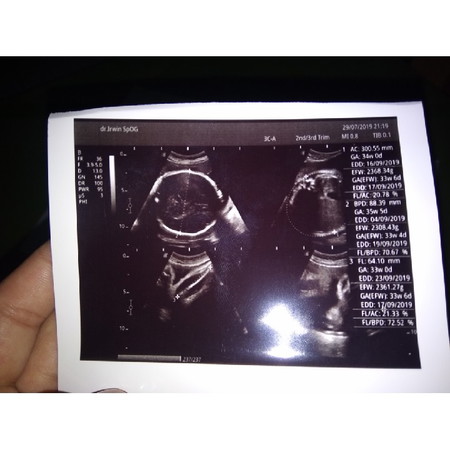

Bun mau tanya ini gimna baca nya yah aku mau tau aku hamil berapa Minggu Bun tolong kasih tau dongbun

35 minggu 5 hr bun